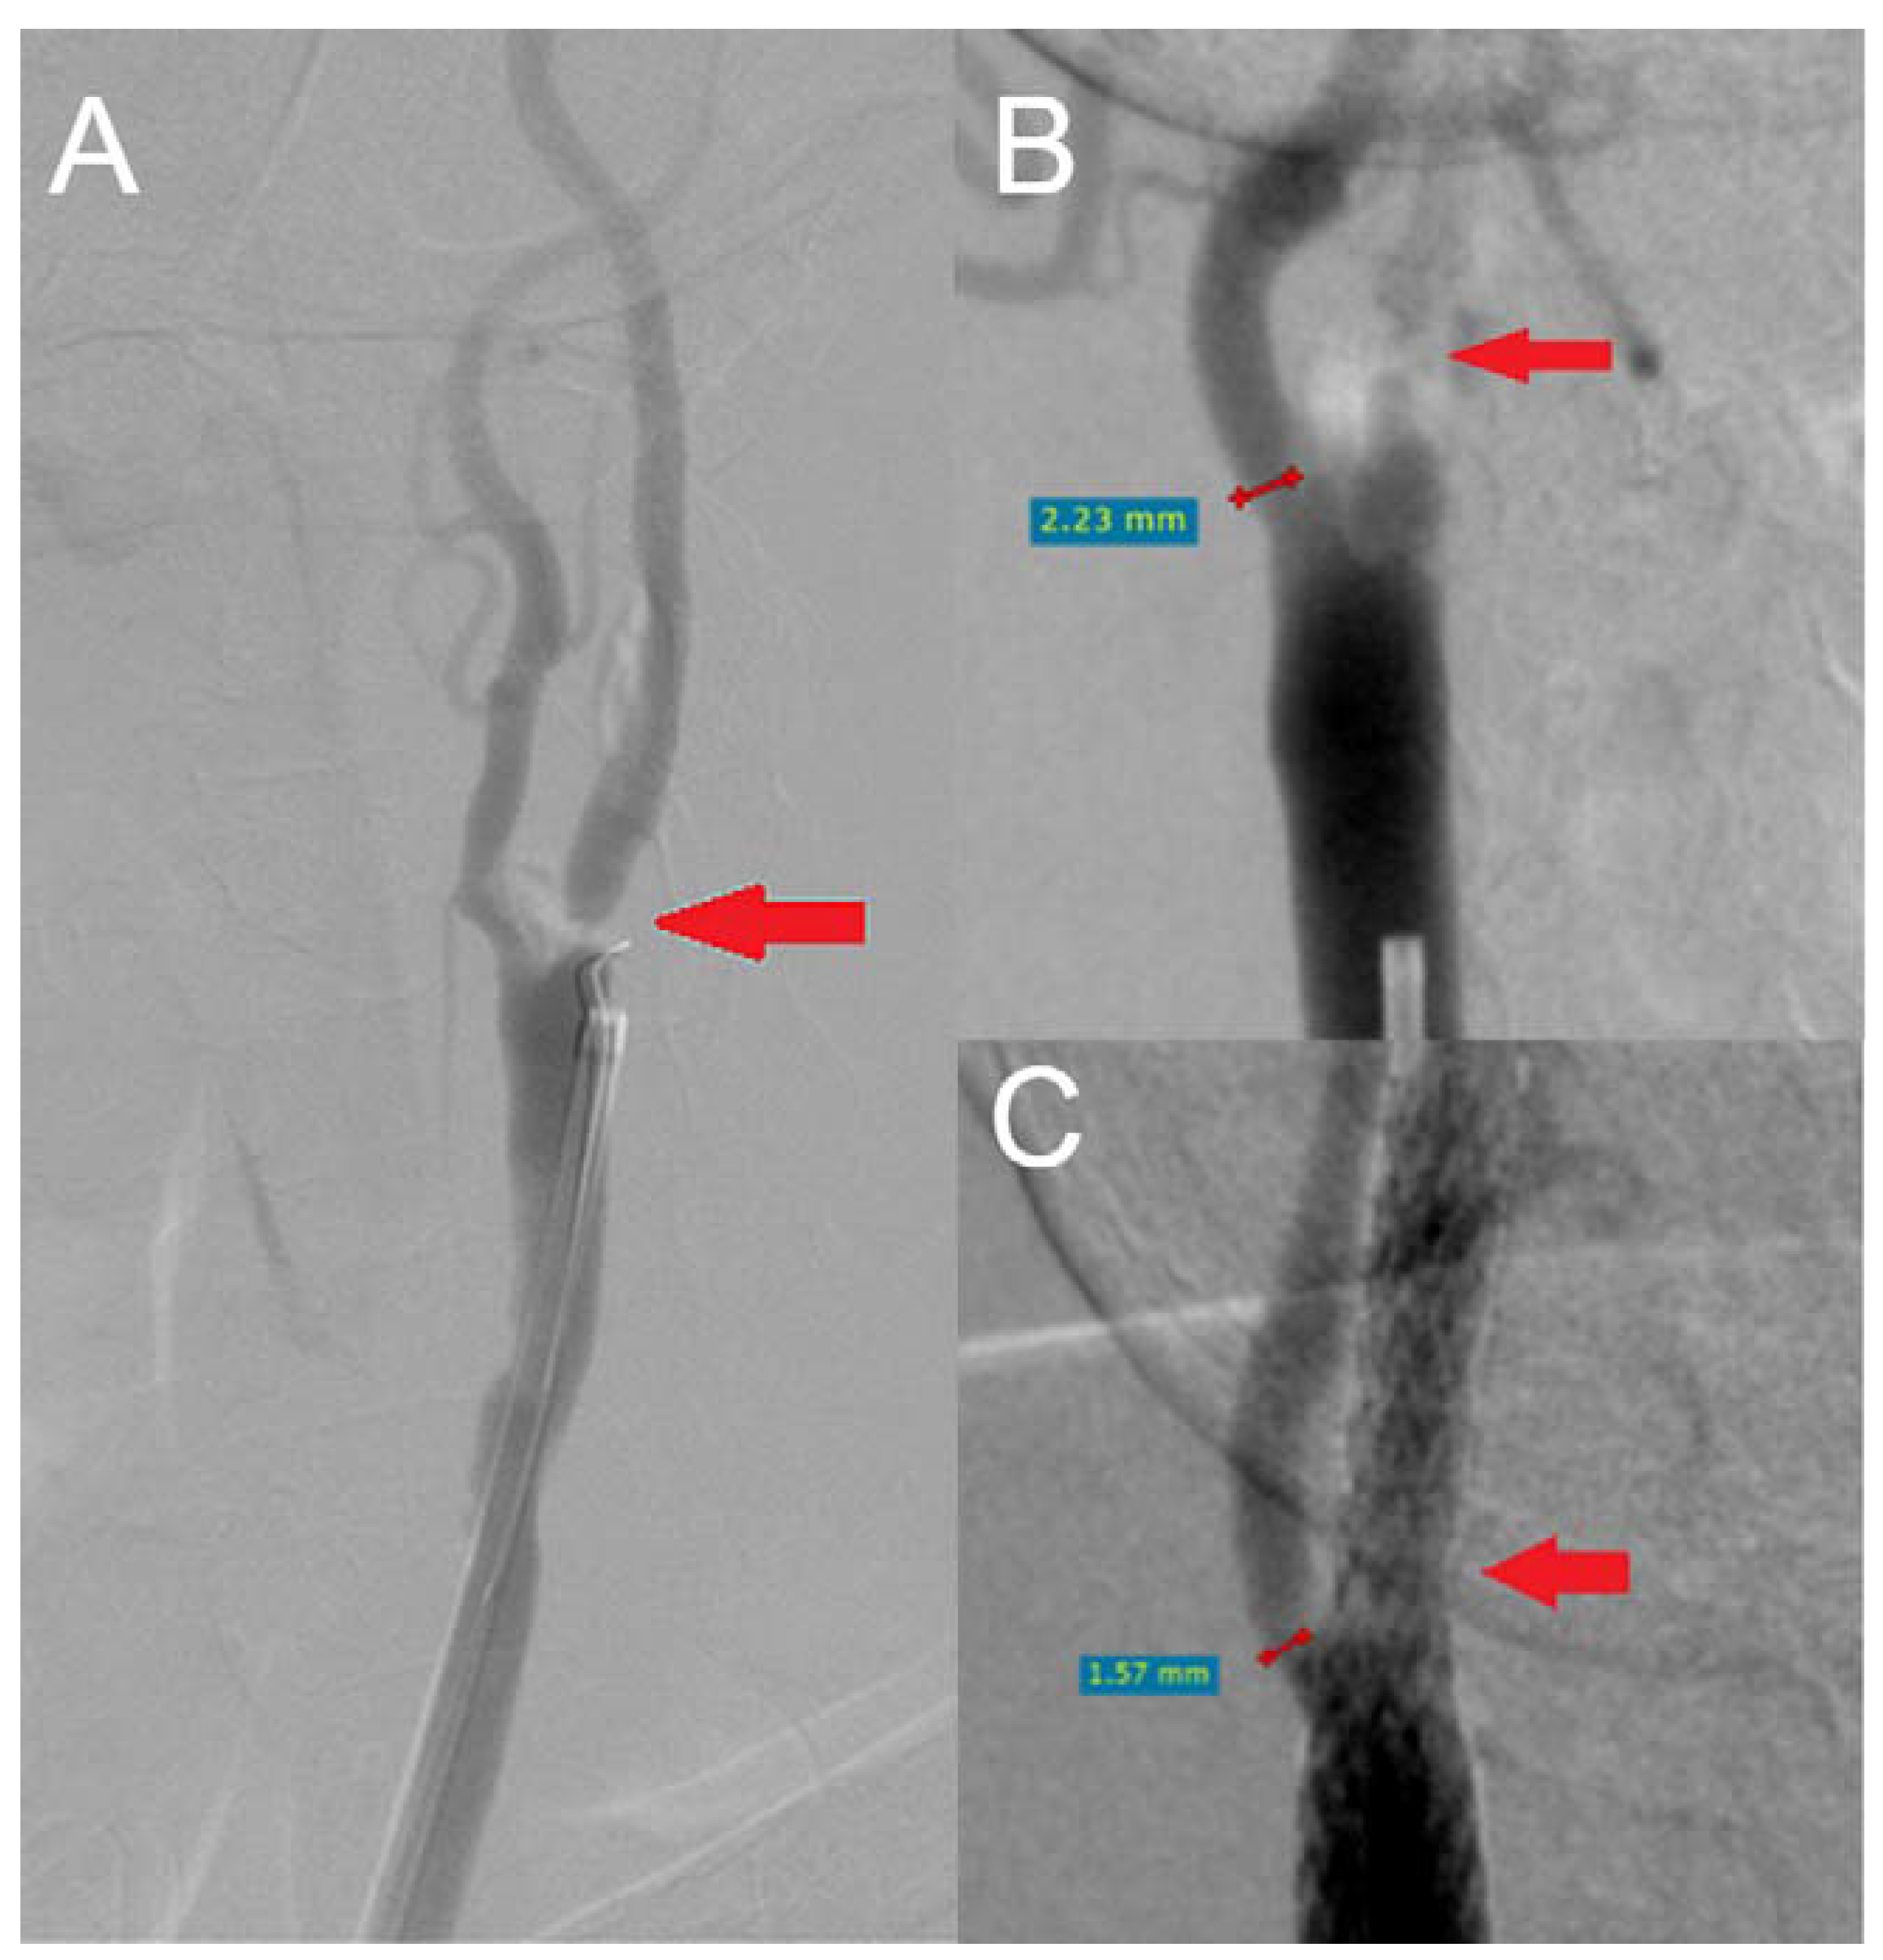

| Preoperative ICA diameter (mm) | 0.8 (0.2–2.7), IQR 0.36 |

| Preoperative ECA diameter (mm) | 4.34 (0.80–8.10), IQR 2.25 |

| Postoperative ICA diameter (mm) | 5.60 (2–9.80), IQR 2 |

| Covering of ECA orifice by a carotid stent | |

| Yes | 144 (94.73%) |

| ECA diameter after CAS (mm) | 3.40 (0–7.70), IQR 2.00 |

| Difference between pre- and postoperative ECA diameter (mm) | 0.9 (−2.20–4.60), IQR 1.73 |

| Difference in post- and preoperative ICA diameter (mm) | 4.92 (1.3–8.7), IQR 1.87 |